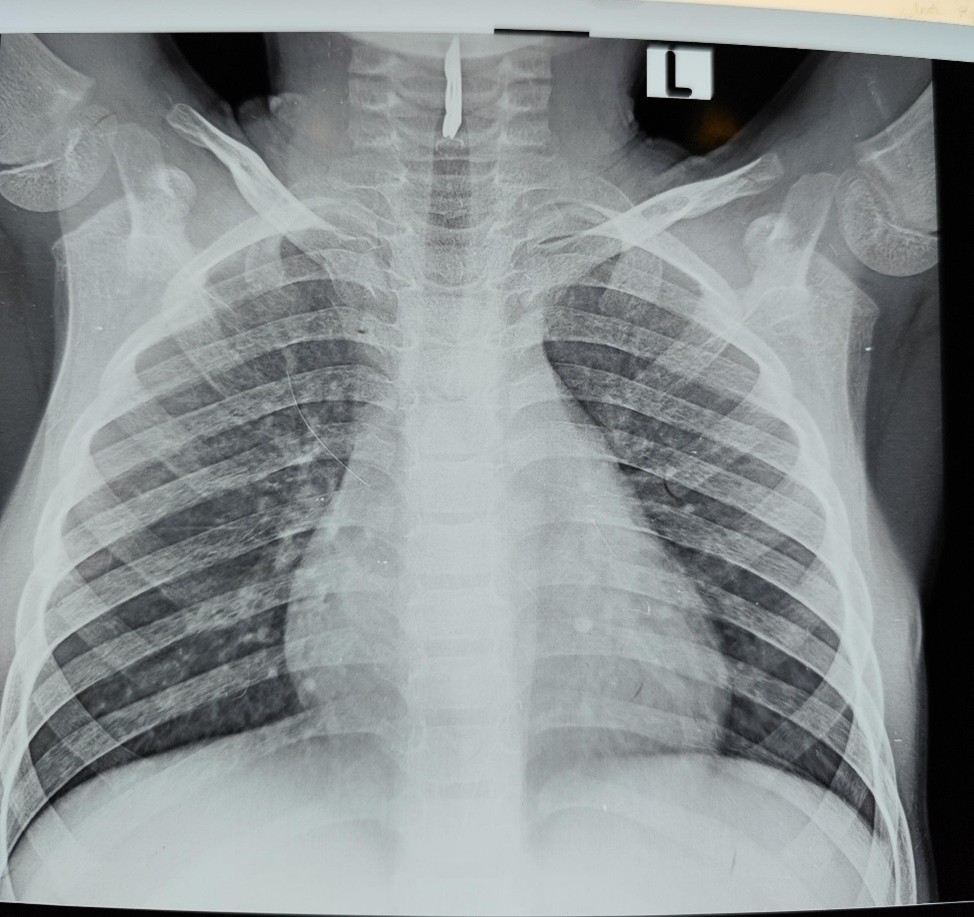

The child was stridulous on examination with nasal flaring, intercostal and subcostal recessions. He was afebrile, not pale, anicteric, not cyanosed, and not dehydrated. He was tachypneic with respiratory rate of 52 cycles/minute, oxygen saturation was 99% in room air, and other vital signs were within normal limits. A soft tissue X-ray of the neck and chest revealed a radio opaque object in the airway at the level of C4–C6 which is the region of the larynx as shown in Figures 1 and 2. A diagnosis of laryngeal foreign body was made.

Figure 1. Soft tissue X-ray of the neck and chest revealing a radio opaque object in the airway (Anterior view).